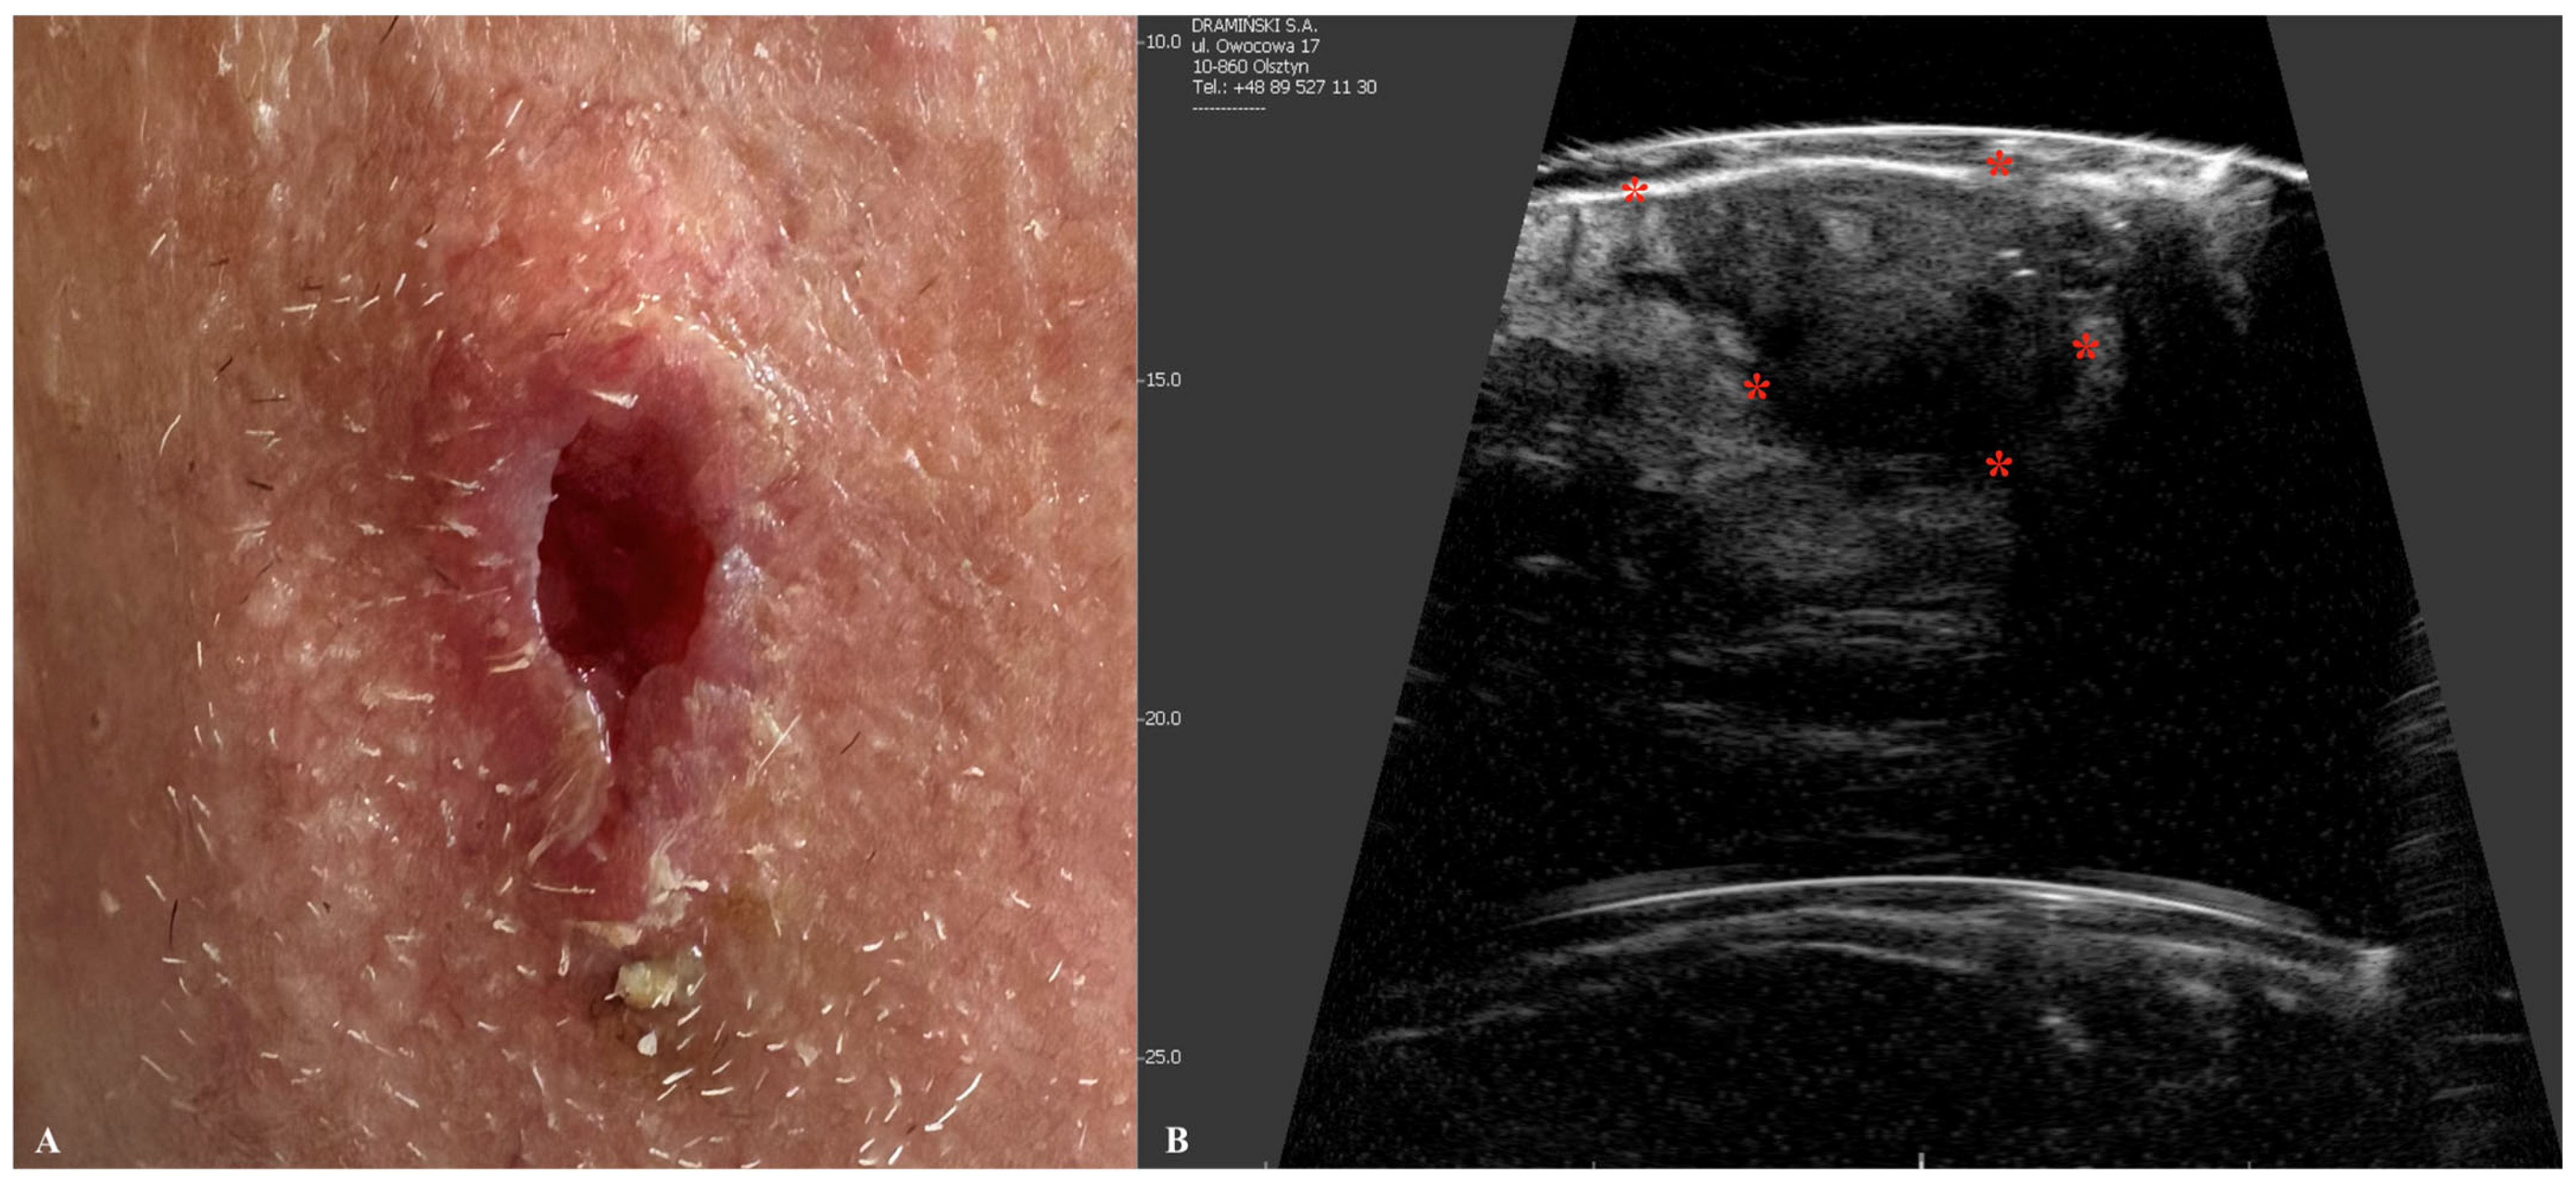

3. Squamous Cell Carcinoma

| Squamous Cell Carcinoma | Hypoechogenic lesion with irregular, poorly defined margins. Epidermal detachment and ulceration are common. More vascularized than BCC. |